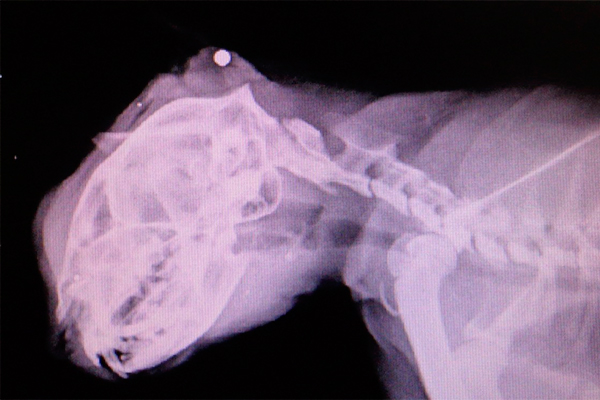

Шанс выжить после выстрела в голову гораздо больше, если пуля вошла в лоб и вышла из затылка, чем если пуля вошла в один висок и вышла из другого . Дело в том, что при попадании в лоб пуля . . .